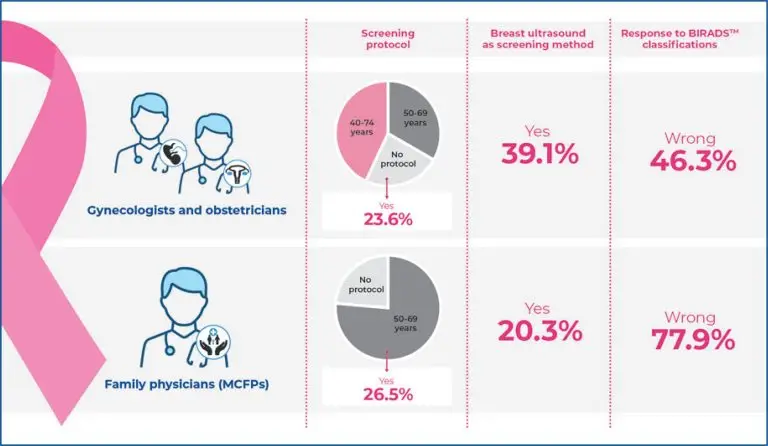

Knowledge related to breast cancer screening programs by physicians in Brazil

Highlights Variability in screening protocols: only 42.8% of gynecologists and obstetricians follow the 40-74 years protocol, while 76.6% of family physicians follow the 50-69 years protocol. High rate of incorrect BIRADS™ interpretation: there were 46.3% incorrect responses among gynecologists and obstetricians and 77.9% among family physicians, highlighting significant knowledge gaps. Misconception about breast ultrasound: 39.1% of gynecologists and obstetricians and 20.3% of family physicians incorrectly consider ultrasound as a screening method. Impact of inadequate training: inadequate training leads to improper […]

Keywords: attitudes; Brazil; Breast neoplasms; Family; Gynecologists; Health knowledge; Mammography; Mass screening; Obstetricians; Physicians; practice; Preventive medicine; Surveys and questionnaires